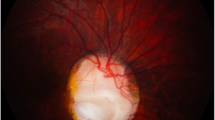

The globes and eyelids were fused at the midline. The continuity of the two superior, and the two inferior lids created a rhomboid-shaped midline palpebral fissure inferior to the proboscis (Fig. 1B). Beneath the lids, anterior eye structures including a transparent cornea and the pupil were not found. A horizontal transverse section through the eyes is shown in Fig. 2A. The eyelids contained well-developed structures including meibomian glands and hair follicles (Fig. 2B). The inner palpebral surfaces and the sclera-like tissue over the eyes were covered by conjunctival epithelium containing numerous goblet cells. The histological sections oriented through the pupil showed a striking absence of corneal differentiation. Corneal epithelium, stroma, or Descemet's membrane could not be identified. Instead, underlying the anterior connective tissue was a mesh-like loose band of tissue covering the front of the anterior chamber. Although RPE was identified, the angle, trabecular meshwork, and iris had failed to form.

Transverse section of the fused eyes. A) Gross view showing two separate lenses (L), retina (R), and partially fused optic nerve (ON). An incomplete septum extends posteriorly from the anterior sclera (asterisk). B) Histological section demonstrating a single common posterior chamber containing laminated and disorganized neural retina. C) Higher magnification of the disorganized retina showing dysplastic rosettes (hematoxylin and eosin B, C).

The gross and histological sections showed a single globe incompletely divided into separate eyes by a partial fibrous septum. The septum extended posteriorly from the anterior sclera separating the two lenses (asterisk, Fig. 2A,B). However, it failed to extend sufficiently in the posterior direction to finish dividing the rest of the eye into separate chambers. The partition was lined by the RPE layer. In some areas the retina showed a near normal laminar structure consisting of well defined inner and outer nuclear layers. However, most regions were disorganized consisting of scattered rosette-like structures (Fig. 2C). A focal region of cartilage and CNS tissue were also found in the dysplastic retina. The retina collected at a single point at the posterior pole forming a fused single hypoplastic optic nerve. The rosettes extended into the optic nerve head, and to some degree down the optic nerve itself. Although there appeared to be one optic nerve, some of the sections suggest the presence of two incompletely separated nerves.